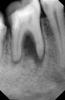

evgenrst Опубликовано 31 мая, 2011 Поделиться Опубликовано 31 мая, 2011 (изменено) Подскажите можно ли вылечить зуб. Он такой 2 года без изменений. Каналы не лечились. Иногда открывается свищ. Болезненных ощущений нет. Врач сказал, что можно попробывать Метапексом. Так ли это? Снимок прикреплен. Спасибо. Изменено 31 мая, 2011 пользователем evgenrst Ссылка на комментарий

Bier Опубликовано 31 мая, 2011 Поделиться Опубликовано 31 мая, 2011 если кармана нет, то действительно можно пробовать. Ссылка на комментарий